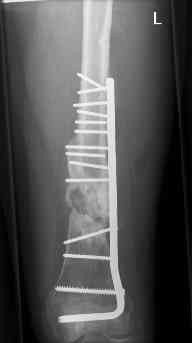

july 05: LISS femur, LCP plate tibia, double recon. plate post. acetabulum

aug 06: blade plate + bone graft

nov 06: revision blade plate

nov 07: persistant non-union distal femur; other fractures healed

uneventfully.